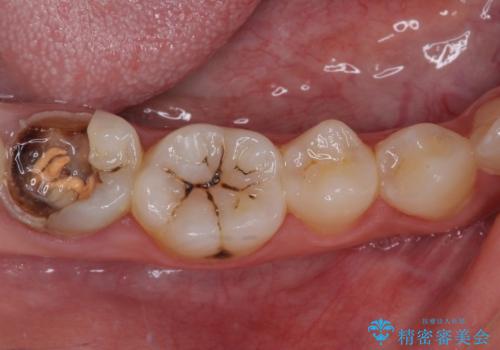

むし歯だらけの奥歯 セラミッククラウンによるむし歯治療

- 奥歯のむし歯を気にして来院された患者様です。

痛みのある歯が多く、根管治療が必要と診断されました。

自身の口腔内への意識が高くなく、汚れが非常に多い方でした。